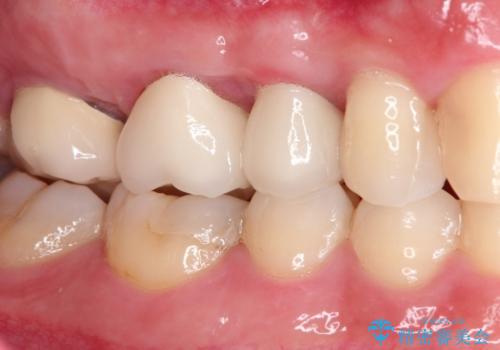

セラミッククラウン。虫歯の治療

- 定期検診にて不良補綴物、及び虫歯を認めオールセラミッククラウンにて治療を行いました。

右上第二小臼歯はカリエス除去中に露髄を認め、部分的断髄法にて歯髄を保存しております。